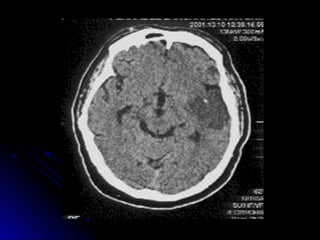

DIAGNOSTICO:DIAGNOSTICO:

Laboratorio. hemograma, glucemia, ionograma, ESD,

tiempo deQuick, KPTT, orinacompleta

Evaluación neurológica

Radiologíatórax frente

ECG y Evaluación Cardiológica, Eco bidi, Doppler

TAC cerebral

RNM (utilidad técnicadedifusión y percusión)

Eco Doppler VasosCuello,

 Angio RNM, Arteriografía

Ubicación de las lesiones en TAC-RNM

HEMORRAGIA

CEREBRAL

AVE HEMORRAGICO

“Cuadro causado por

rupt ur a vascular e

irrupción de sangre en el

parénquima cerebral,

acompañado de

hipert ensión endocraneana

y por lo gener al